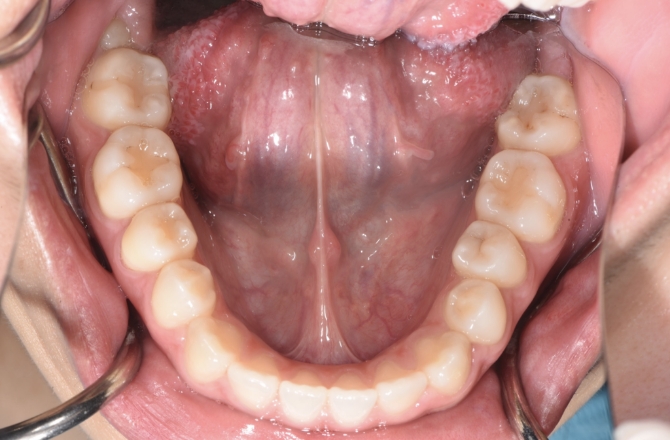

CASE 01歯並びと咬み合わせを治したい

Before

Before

-

After

After

| 矯正種類 | 成人矯正 |

|---|---|

| 抜歯有無 | 上下抜歯 |

| 治療期間 | 3年 |

| 費用 | 990,000円 |